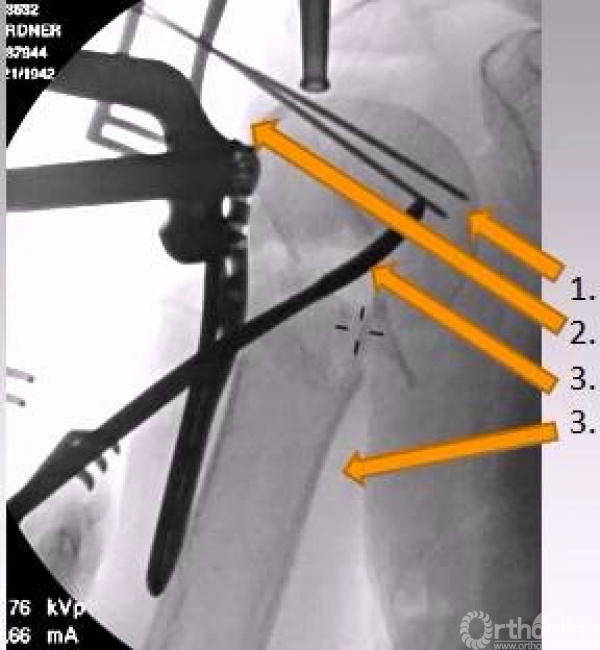

复位技巧

1.克氏针摇杆技术;

2.肩袖缝线牵拉技术;

3.骨拨翘拨技术;

正位的翘拨复位

腋位的翘拨复位